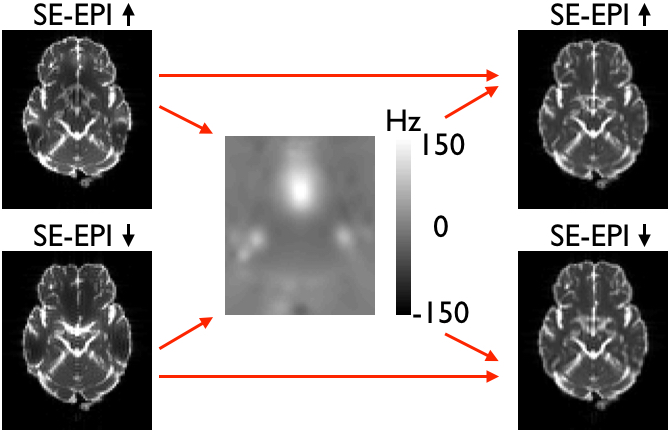

|

| Pairs of SE- and GE-EPI images acquired with opposing phase-encode directions. Note how the distortions are the same as evidenced by the similar shape. But that in the GE-EPI images there are also signal dropout that differ between the two image. |

This means that the model underlying topup is not valid for these data, and the consequence will be that topup will attempt to "explain" the observed differnces due to signal modulation as being caused by distortions. It can do a surprisingly good job at that, producing two "corrected" images that look very similar. But that is potentially at the cost of an estimated field that is far from the true field, and "corrected" images that are potentially even worse distorted than to start with. Below is a comparison between a field estimated from a pair of Spin-Echo(SE)-EPI images and from a pair of GE-EPI images. The images have been simulated using the physics based MR-simulator POSSUM, so the truth is known. As can be seen the field estimated from the GE-EPI pair is almost the negation of the true field. This means of course that the "corrected" images are worse than the original images.